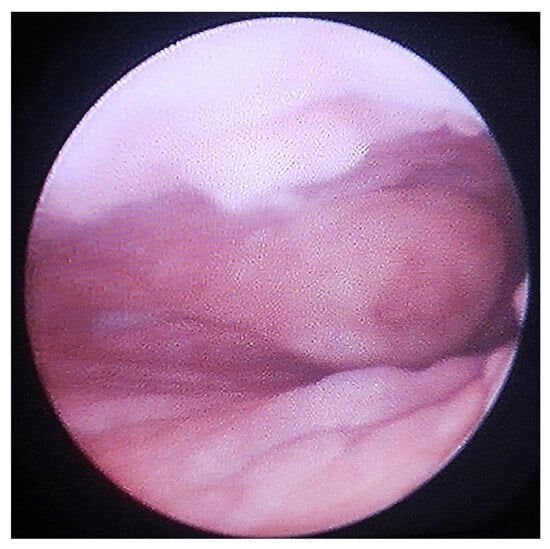

Figure 3.

Vaginoscopy demonstrating cervix.